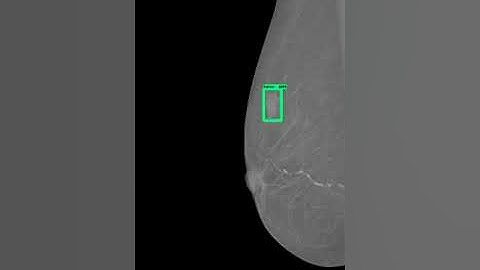

Breast Cancer Detection From Ultra Sound Images Using Deep Learning